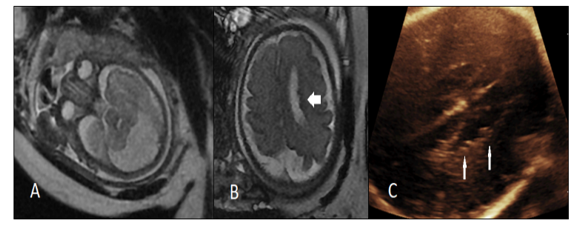

Figure 3. A 30 weeks fetus with severe ventriculomegaly and IVH was referred for fetal MRI. A, B, C) T2-weighted, T1-weighted and DWI images (respectively) showed unilateral severe ventriculomegaly y, periventricular edema and acute IVH. In fig A, focal extension of hemorrhage to adjacent parenchyma (arrow) is evident (IVH grade 4). But this parenchymal extension was not detected by neurosongraphy. D, E) Another 23 weeks fetus with recent radiofrequency ablation of co-twin showed germinal matrix hemorrhage (arrow) and whole brain infarct in DWI (E) with normal neurosonography.

Among all enrolled cases, NSG-MRI discordance was found in 22.9% (32) of fetuses, all showing additional findings in MRI, while none showed additional or contradicting findings on NSG (Figure 2). Table 3 describes the NSG findings in each of these 32 cases and shows any additional MRI features that were not visible on NSG. Interestingly, 4 fetuses had normal brains in NSG exams but were diagnosed with IVH/GMH in MRI. MRI was superior to NSG to detect intracranial hemorrhage and cortical malformations and offered a more accurate estimation of the extension of cortical malformation. Table 3 also outlines the final delivery outcome and duration of follow-up for each of these cases.